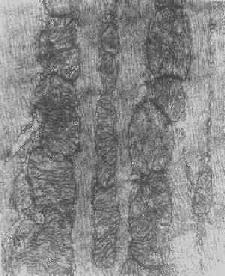

四、线粒体线粒体(mitochondrion)是细胞内主要的能量形成所在,故不论在生理上或病理上都具有十分重要的意义。 线粒体为线状、长杆状、卵圆形或圆形小体,外被双层界膜。外界膜平滑,内界膜则折成长短不等的嵴并附有基粒。内外界膜之间为线粒体的外室,与嵴内隙相连,内界膜内侧为内室(基质室)(图1-8)。在合成甾类激素的内分泌细胞(如肾上腺皮质细胞、卵甾滤泡细胞、睾丸的Leydig细胞等),线粒体嵴呈小管状。内外界膜的通透性不同,外界膜的通透性高,可容许多种物质通过,而内界膜则构成明显的通透屏障,使一些物质如蔗糖和NADH全然不能通过,而其他物质如Na+ 和Ca 2+等也只有借助于主动运输才能通过。线粒体的基质含有电子致密的无结构颗粒(基质颗粒),与二价阳离子如Ca2+及Mg2+具有高度亲和力。基质中进行着β氧化、氧化脱羧、枸橼酸循环以及尿素循环等过程。在线粒体的外界膜内含有单胺氧化酶以及糖和脂质代谢的各种转移酶;在内界膜上则为呼吸链和氧化磷酸化的酶类。 线粒体是对各种损伤最为敏感的细胞器之一。在细胞损伤时最常见的病理改变可概括为线粒体数量、大小和结构的改变: 1.数量的改变 线粒体的平均寿命约为10天。衰亡的线粒体可通过保留的线粒体直接分裂为二予以补充。在病理状态下,线粒体的增生实际上是对慢性非特异性细胞损伤的适应性反应或细胞功能升高的表现。例如心瓣膜病时的心肌线粒体、周围血液循环障碍伴间歇性跛行时的骨骼肌线粒体的呈增生现象。 线粒体数量减少则见于急性细胞损伤时线粒体崩解或自溶的情况下,持续约15分钟。慢性损伤时由于线粒体逐渐增生,故一般不见线粒体减少(甚至反而增多)。此外,线粒体的减少也是细胞未成熟和(或)去分化的表现。 2.大小改变 细胞损伤时最常见的改变为线粒体肿大。根据线粒体的受累部位可分为基质型肿胀和嵴型肿胀二种类型,而以前者为常见。基质型肿胀时线粒体变大变圆,基质变浅、嵴变短变少甚至消失(图1-9)。在极度肿胀时,线粒体可转化为小空泡状结构(图1-10,图1-11)。此型肿胀为细胞水肿的部分改变。光学显微镜下所谓的浊肿细胞中所见的细颗粒即肿大的线粒体。嵴型肿较少见,此时的肿胀局限于嵴内隙,使扁平的嵴变成烧瓶状乃至空泡状,而基质则更显得致密。嵴型肿胀一般为可复性,但当膜的损伤加重时,可经过混合型而过渡为基质型。 线粒体为对损伤极为敏感的细胞器,其肿胀可由多种损伤因子引起,其中最常见的为缺氧;此外,微生物毒素、各种毒物、射线以及渗透压改变等亦可引起。但轻度肿大有时可能为其功能升高的表现,较明显的肿胀则恒为细胞受损的表现。但只要损伤不过重、损伤因子的作用不过长,肿胀仍可恢复。 线粒体的增大有时是器官功能负荷增加引起的适应性肥大,此时线粒体的数量也常增多,例如见于器官肥大时。反之,器官萎缩时,线粒体则缩小、变少。

图1-8 心肌细胞线粒体